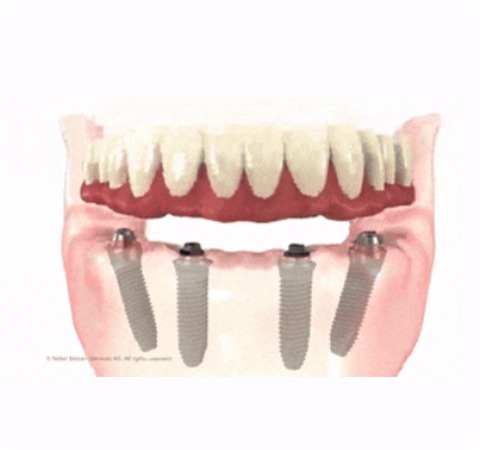

All-on-4 讓患者在短短一天內即刻擁有全新的牙齒,從而恢復咀嚼功能和好看的外觀。

原理是透過顎骨做植體的支撐,利用類似斜張橋段般的特殊力學設計提供穩固支撐力,幾乎無須進行補骨手術,而是讓力量合理分散到四支或以上的植體,最後在植體上固定特殊客製的假牙。

想像你的嘴巴是一座橋,而牙齒就是支撐這座橋的柱子。

All-on-4 就像一種特殊的建造方法,可以用四根或以上超級堅固的柱子來重新建造這座橋,不僅讓嘴巴的「橋」迅速恢復功能,還讓外觀看起來自然,就像從未缺牙一樣,而且時間只要短短一天!